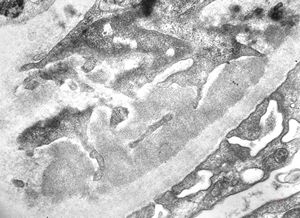

F,14y. | Alport syndrome - split and laminated, thick/thin basement membranes